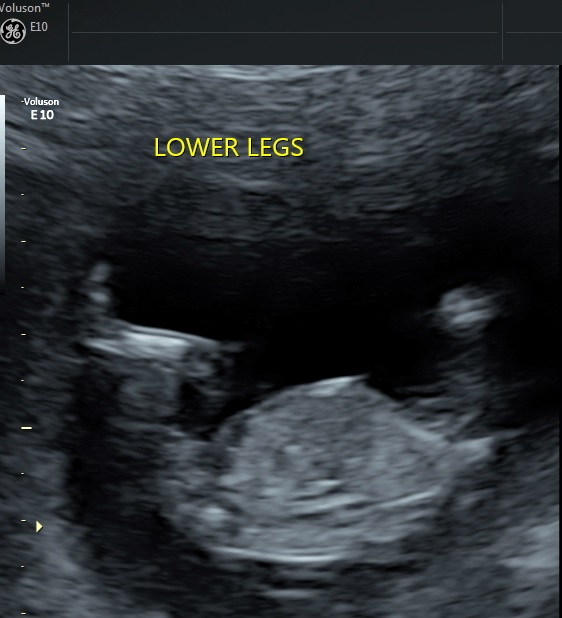

Does this picture show anything? Tech did guess boy, but she didn't know about nub theory and she went to look between the legs and took this pic saying it looked like boy bits.

I'm thinking boy. It looks like there is stacking. On the other hand, it's not classic party hat because it's a fork on top instead of a ball.

Hmm, that's a tricky one! My initial thought was blue, but then I scrutinised it a bit and thought it looks more pink....?

I will say, the Dr told me boy at my 13+4 US, but she is very much a girl. So it's just too early for a potty shot! But hoping for pink!!